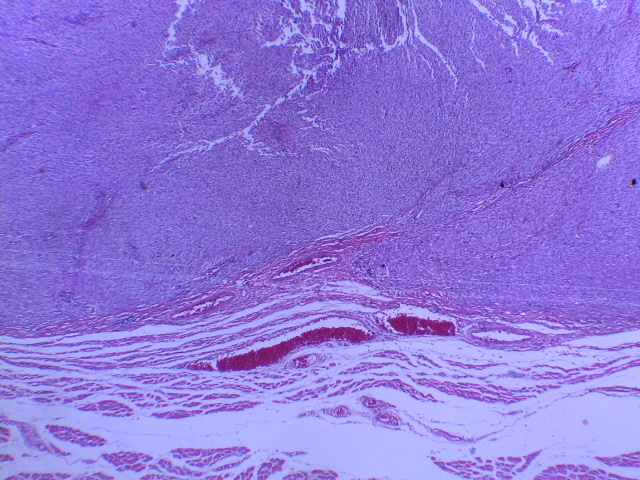

Diagnóstico:

Tumor del estroma gastrointestinal en orbita y agregar la referencia : Orbit. 2012 Apr;31(2):129-31.